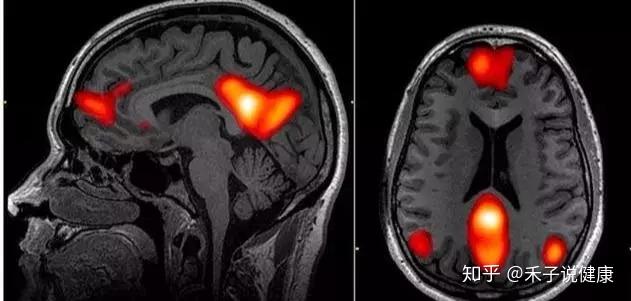

3.功能磁共振的研究还发现了抑郁症相关的大脑网络活动异常。

什么是大脑网络?在最近 20 年的大脑成像研究积累下,脑科学家发现,大脑执行任何一个功能都不是某个单独的脑区就可以完成的。大脑在执行任务的时候,往往需要调用大脑当中距离遥远的不同区域,这些脑区会以网络的形式协同合作。比如当你专注于看书的时候,你的大脑前部的注意网络就会被激活,让你保持专注;而当你无所事事做白日梦的时候,大脑前部、中部和两侧部分脑区都会被激活,这些脑区构成的网络叫做默认网络,这个默认网络涉及到的功能就是自省、想象、做白日梦等等。

4.那么和抑郁症相关的异常大脑网络包括了哪些呢?

研究发现,大脑网络负责情绪调节、反刍性思维、兴趣缺失有关的奖赏回路,以及自我意识,在抑郁症病人的大脑当中都有或多或少的异常,对应到具体的位置,就是抑郁症患者大脑的杏仁核活跃程度和连接程度会增强,膝下前扣带回活跃程度会增强,而脑岛和背侧前额叶的活跃程度会降低。不过这些脑成像研究当中观察到的变化只是数量庞大的病人群体的平均趋势,如果具体到每一个患病的个人,病人之间的个体差异其实非常大,甚至可能和平均的趋势毫无关系。